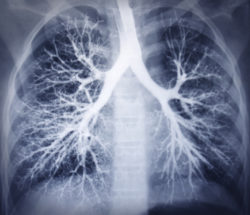

lung xrayIncreasing studies have illustrated that exposure to asbestos can considerably increase lung cancer risk. Asbestos take-home exposure is also among the significant risks in causing and developing lung cancer.

The lining of the bronchi, airways in the respiratory tract that conducts air into the lungs, is where most asbestos lung cancer begins. It can, however, also begin in the trachea, bronchioles, or alveoli. It is common for lung cancer to develop slowly as well, but it is also acknowledged that once developed, it can spread to other parts of the body.